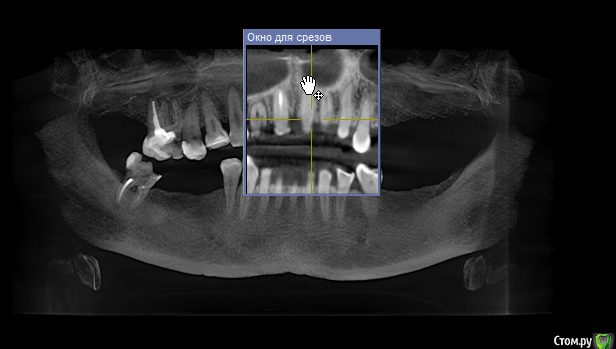

elesilchenko@yandex.ru Опубликовано 18 октября, 2016 Поделиться Опубликовано 18 октября, 2016 Здравствуйте! Подскажите, пожалуйста, возможна ли дентальная имплантация на НЧ без применения костной пластики? И возможно ли спасти зубы с кистами на ВЧ ?Результаты КТ: http://files.mail.ru/1F70A64348084F03ACC722DA9E76BD2B Ссылка на комментарий

elesilchenko@yandex.ru Опубликовано 18 октября, 2016 Автор Поделиться Опубликовано 18 октября, 2016 Добрый вечер! Я в процессе выбора, кто предлагает базальную имплантацию внизу (ВЧ я пока не рассматриваю к имплантации) , кто съемные протезы это на НЧ. По поводу ВЧ тоже разные мнения: 1. Можно полечить, т.к. проблемы с эндодонтией 16 и 12, где небольшой воспалительный процесс.2. 16 удалить, 12 попытаться полечить. Сунус-лифтинга и костной пластики боюсь. Ссылка на комментарий

IvanK Опубликовано 18 октября, 2016 Поделиться Опубликовано 18 октября, 2016 Судя по скудной информации из скриншотов:кости , скорее всего, будет достаточно Вам нужно найти Врача, которому доверяете и довериться) Сходите на пару-тройку очных консультаций Ссылка на комментарий